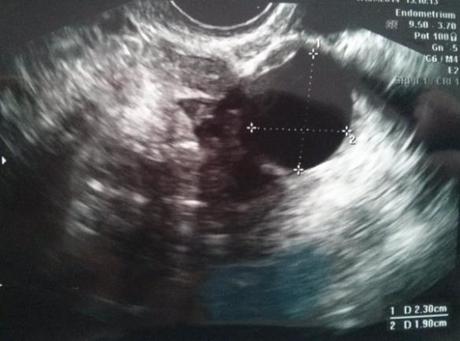

En la siguiente foto tenéis la ecografía. En la primera foto se mide el residual, y en la segunda el mediano. En la segunda foto se ve mejor ese otro “foliculín” entre los dos más grandes.

Le tuve que recordar la existencia del folículo residual, tomó medidas y comprobó que efectivamente se trataba del mismo. En ese mismo ovario, el derecho, había otros dos folículos, de los cuales, uno era mediano y otro pequeño.